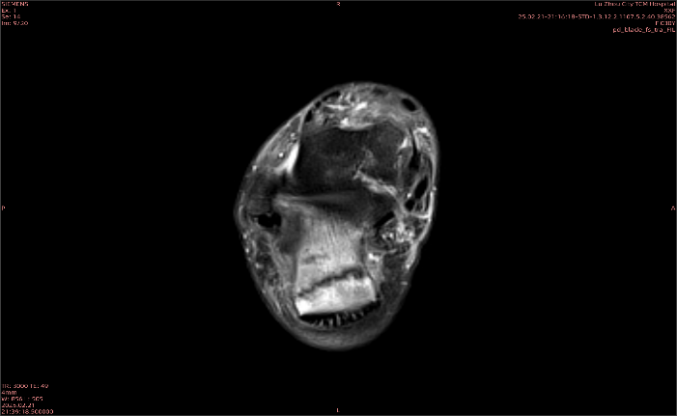

隱性骨折在MRI表現(xiàn)為T1WI序列上見由關(guān)節(jié)面向骨干走行的形態(tài)各異低信號(hào)區(qū),有線狀、條狀、紊亂低信號(hào),信號(hào)強(qiáng)度不均勻。與T1WI低信號(hào)改變相對(duì)應(yīng)部位在T2WI上表現(xiàn)為相應(yīng)形狀的高、低混雜信號(hào),且部分低信號(hào)周圍可見高信號(hào)水腫改變。STIR序列圖像上病灶呈顯著高信號(hào),與信號(hào)被抑制的臨近正常骨髓形成鮮明對(duì)比,分界也較T2WI成像更為清楚。脂肪組織抑制技術(shù)是MRI的一個(gè)重要性能,脂肪抑制技術(shù)在MRI應(yīng)用中可以改善組織對(duì)比和增加病變顯示機(jī)會(huì),這樣骨髓的脂肪抑制后就不會(huì)有任何信號(hào),而隱性骨折線及骨髓水腫的異常高信號(hào)就會(huì)更加明顯的顯示出來。

舉例圖像

圖1

專業(yè)解釋看不懂沒關(guān)系,大家看圖1和圖2就可以了,這是同一個(gè)患者跟骨的磁共振和CT圖像,圖1的紅色箭頭指示的黑線就是磁共振圖像顯示的骨折線,一目了然。而對(duì)比圖2的CT圖像上并未顯示異常。

這下大家明白了吧,如果懷疑隱匿性骨折優(yōu)先選擇磁共振檢查